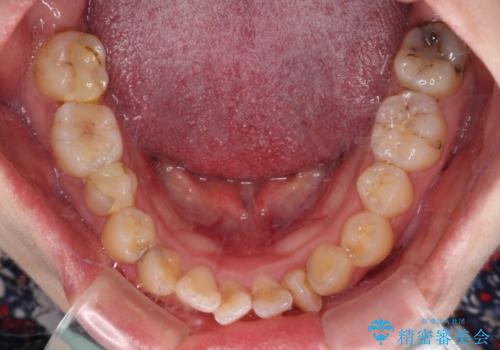

- 上下の歯が非接触であり、八重歯やむし歯を気にして来院された患者様です。

下顎骨の左右偏位はあるものの、上顎骨幅が相対的に狭い状態であったので、奥歯の咬み合わせが非常に乱れていました。

急速拡大装置により上顎骨幅を側方に拡大し、それを利用して八重歯を歯列に納めることにしました。